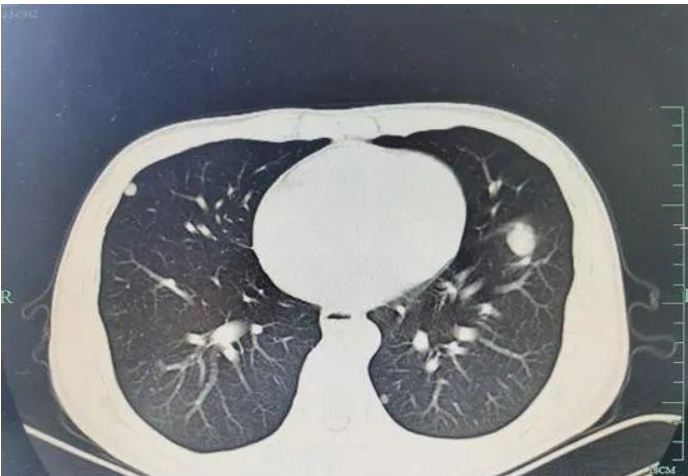

「今年2月 , 我左上腹开始感觉刺痛不适 , 有时左下腹也跟着痛 , 厉害时痛得浑身冒汗 。 」小吴说 , 3月23日 , 忍受不了腹痛的他 , 到医院做了腹部电脑断层摄影(CT) , 检查结果让他大吃一惊 , 肝多发占位 , 可能是肝癌 。

▼小吴肚子痛了一个多月 , 到医院一查 , 竟已是肝癌晚期 。

一家人始终不敢相信这个检查结果 , 直到最近小吴转院到了市西溪医院 。 余吉仙主任医师查看小吴的病历后 , 让他复查了CT , 检查结果并没有出现转机 , 他的肝脏上长有一颗巨大肿瘤 , 伴肝内转移、肺转移 。